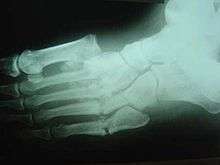

Radiologic findings

First, it is important to recognize that two types of abnormality may be detected. One is termed atrophic, in which there is osteolysis of the distal metatarsals in the forefoot. The more common form of destruction is hypertrophic joint disease, characterized by acute peri-articular fracture and joint dislocation. According to Yochum and Rowe, the "6 D's" of hypertrophy are:

Destroyed Tarsometatarsal joints in the medial left foot, with fracture and dislocation of fragments; these are classic findings. Also note loss of the foot arch and acquired flat foot (pes planus) deformity.